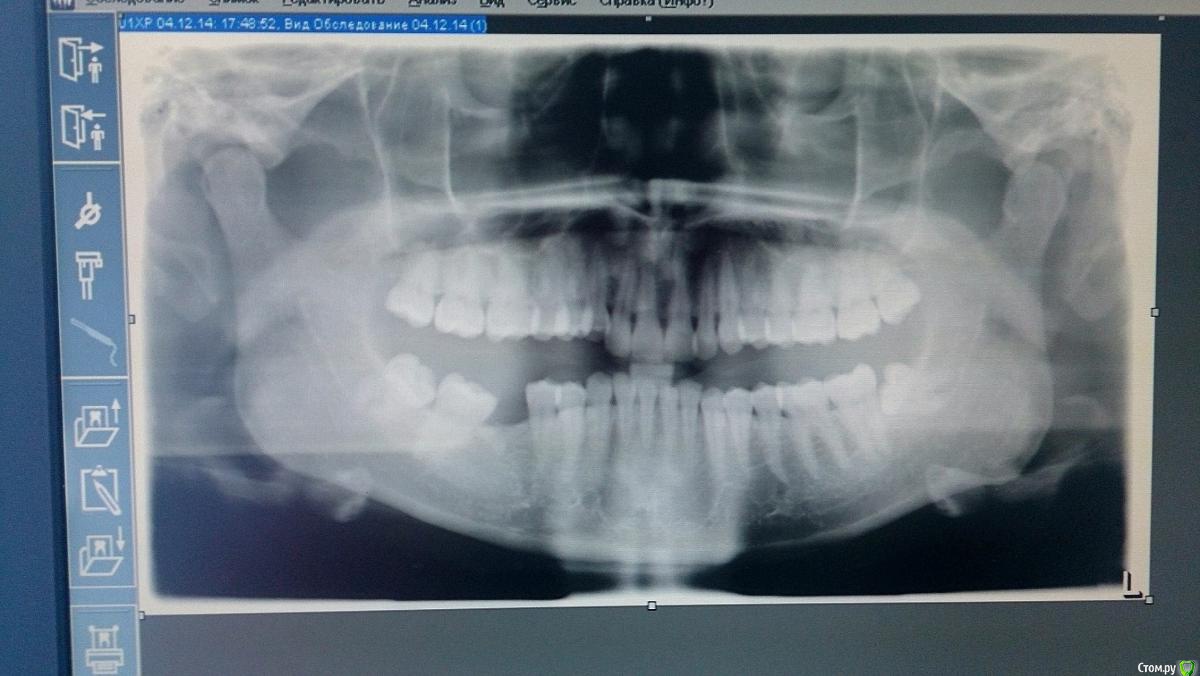

Лефффка Опубликовано 23 апреля, 2015 Автор Поделиться Опубликовано 23 апреля, 2015 Добрый день! Сходила я в клинику, оказывается чтоб взять свои снимки это стоит 500руб Причем у меня есть только снимок ОПГ, а что такого РПГ в рентген кабинете знать не знают Вообщем я попросила показать мне снимок на экране и сфотографировала на телефон,бесплатно А ведь эта клиника считается лучшей у нас в городе Ссылка на комментарий